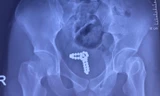

Trong lúc khám nghiệm tử thi, bác sĩ tìm thấy dị vật trong ruột nạn nhân, sau đó được xác định là một bao cao su lạ mắt đựng trong hộp nhựa trong mờ. Gắn liền với dị vật là cái nhãn ghi tên của nạn nhân. Chưa dừng lại ở đó, bác sĩ cũng phát hiện một quả bóng bàn gắn vào ống xi lanh nhựa trong trực tràng của người đàn ông.

![]() |

| Bóng bàn được tìm thấy trong trực tràng của người đàn ông. |